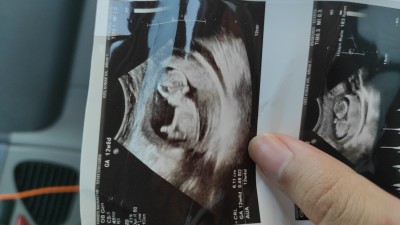

Kızlar selam 13 haftalık gebeyim doktor kordon bacak arasında diye cinsiyet söyleyemedi tecrübeli anneler yorum yapabilir mi coook merak ediyooorum

Gebelik haftası 13+3

Kız erkeklerin çeneleri yukarı bakıyor :P

Erkeğe benziyor ama bilemedim:)

Erkeğe benziyor erkeklerin hem çenesi aşaya bakar kızlarınki yukarda olur bana öyle demişlerdi 33 h hamileyim inşallah nasip olursa oğlum olcak bizimde udroson fotoraflarımız hep böyleydi cenesi eyik ve doktor banada yatısı erkeğe benziyor demişti